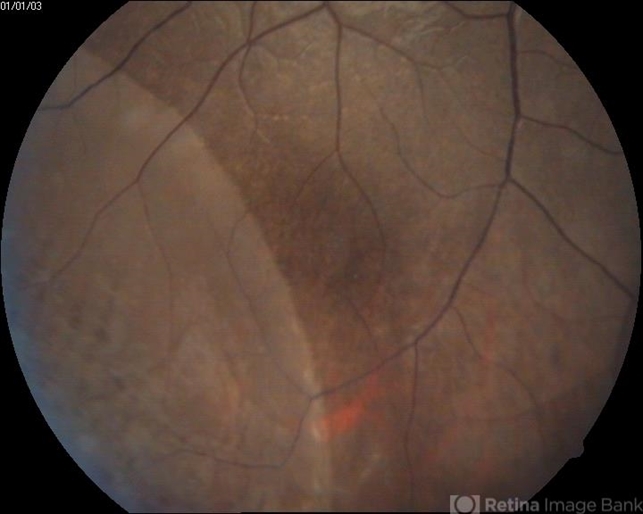

- bullous retinoschisis

- Retinoschisis detected on routiene examination.